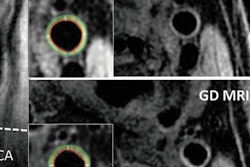

Images of the carotid artery bifurcation in two different patients using vMOT (A and B, orange boxes) and B-mode ultrasound (B, green boxes). Image courtesy of RSNA."Rapid characterization of tissue function and molecular composition is limited with [standard imaging] modalities, which commonly results in poor diagnostic accuracy and ineffective treatments," Razansky said in a statement. "Unlike most other clinical imaging modalities mainly looking at late-stage anatomical manifestations of diseases, vMSOT is capable of sensing specific molecules in tissues without administration of contrast agents."

To test the technique, the group acquired vMSOT images of 16 individuals who previously underwent conventional ultrasound exams. The vMSOT device provided an effective field-of-view of approximately 2 cm3 with the potential for depth adjustment to as much as 30 mm, all in real-time. Images captured with the device also showed considerably fewer motion and blurring artifacts than are typically visible on ultrasound scans, according to the researchers.

A key advantage of vMSOT is that it can visualize the carotid artery, internal carotid artery, and external carotid artery in a single volumetric image frame -- allowing for 3D volume rendering with a single shot without the need for probe scanning, according to the authors. In contrast, obtaining a full view of the carotids with ultrasound requires a lengthy acquisition time and the need to alternate between various 2D cross-sectional views.